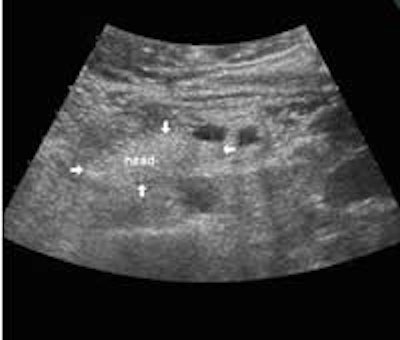

The following study describes anatomical landmarks in the ordinary pancreas of a thin patient:

Transverse planes in caudal direction:

- The lower end of the uncinate process is often overlooked, probably because of its tapered form, which makes it blend with the surrounding fat tissue and the duodenum. Longitudinally, the head of the pancreas is often around 7 cm long, and pathology of the pancreas is often located in the difficult bottom area.